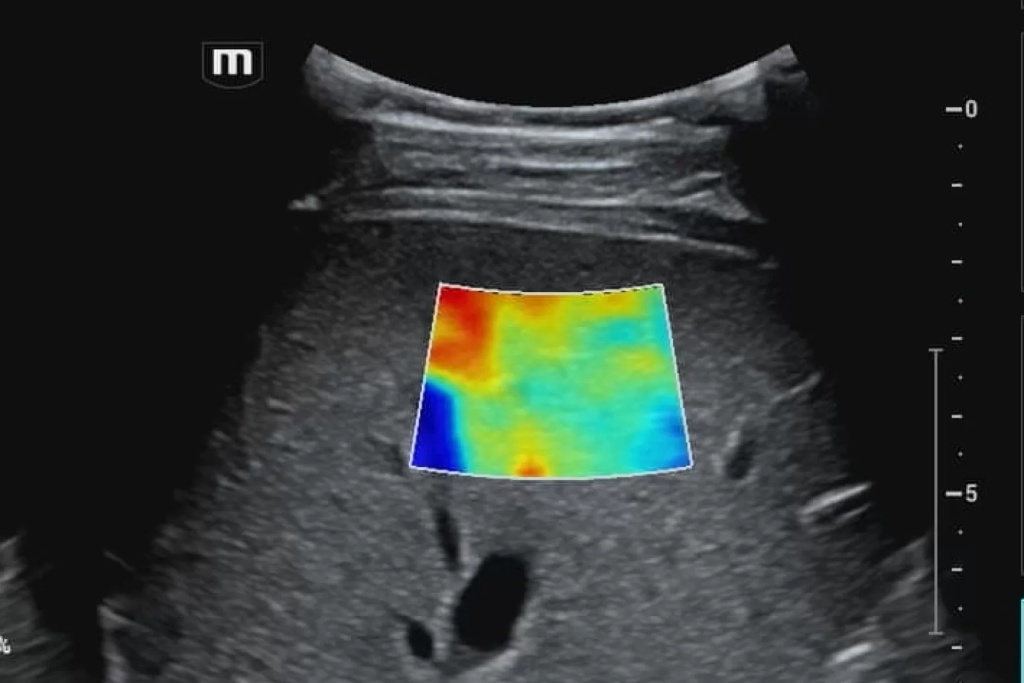

Для проведения диагностики врач использует современные ультразвуковые аппараты с уникальными режимами, позволяющими оценить степень проникновения ультразвуковых волн в ткани. Медицинский специалист также применяет специализированные техники и протоколы исследования для анализа конкретных акустических проблем.

Примером ситуации, требующей диагностики затрудненного акустического доступа, может быть исследование органов брюшной полости у пациентов с избыточным весом, где жировые отложения могут оказать существенное влияние на качество получаемых изображений.

11.jpg